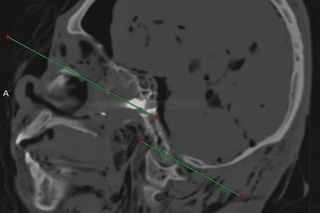

Po trzech miesiącach, w listopadzie 2024 roku Suchir Balaji został znaleziony martwy w swoim mieszkaniu w San Francisco w dzielnicy Mint Hill. Miał poważną ranę głowy, obok niego leżał pistolet, który legalnie nabył w styczniu 2024 roku. Sprawę oficjalnie uznano za oczywiste odebranie sobie życia. Ale rodzice mężczyzny, Poornima Ramarao i Balaji Ramamurthy nie uwierzyli w to. Byli pewni, że sprawa jest podejrzana, bo syn nie wykazywał żadnych skłonności depresyjnych i miał plany na przyszłość, umawiał się m.in. na rozmowy kwalifikacyjne i dostawał bardzo intratne propozycje. Jak pisze "Daily Mail", zlecili niezależne ekspertyzy dwóm lekarzom radiologom. Medycy nie wiedzieli, czyje prześwietlenie czaszki oglądają. Orzekli, że pacjenta trafiły dwie kule, a na jego ciele znaleźli obrażenia, o których oficjalna autopsja milczy.

"Druga kula prawdopodobnie weszła przez usta, nie widać wyraźnej rany wlotowej, ale utkwiła w tylnej części gardła u podstawy czaszki/stożka" - napisał w raporcie dr Daniel Cousin z Radsurity w Weston na Florydzie. Jak podkreśla matka 26-latka, ekspertyza ujawniła obrażenia języka, które nie mogły powstać przy strzale w czoło. Do tego Balaji miał złamaną kość policzkową i uraz z boku głowy oraz ranę na kolanie. Zastrzelił się dwa razy i jeszcze pobił? To nie wszystko. Rodzice komputerowca zlecili też badania toksykologiczne, które ujawniły, że w chwili śmierci w organizmie 26-latka były alkohol i ślady tak zwanej pigułki gwałtu. Matka i ojciec Suchira Balaji nie mają wątpliwości - "to była napaść". Zapowiadają ujawnienie większej ilości materiałów.